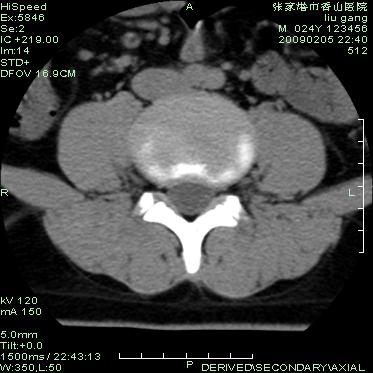

以下是引用hhcckk在2009-3-11 15:43:00的发言:[br]3、4、5腰椎及骶1椎体前上缘不规则,椎间隙改变不明显,结合患者年龄轻考虑:脊椎骨软骨病可能性大[br][br]脊椎骨软骨病又称青年性驼背(scheuerman)。[br][br]1964年sorenson首先提出x线影像学诊断标准:胸段脊柱至少3个相邻椎体有5°或5°以上楔形改变。椎体的楔形变是scheuermann病的基本特点,还可以有其它一些特征,如椎间隙变窄、schmorl结节、椎体终板变窄、不规则或扁平,顶椎前后径增长。

以下是引用随光逐影在2009-3-11 14:43:00的发言:[br]平片:l3、4、5及s1前上缘见类似“切角征”。[br]ct扫描:腰椎多个节段椎间盘向椎体内(椎体前部)突出。